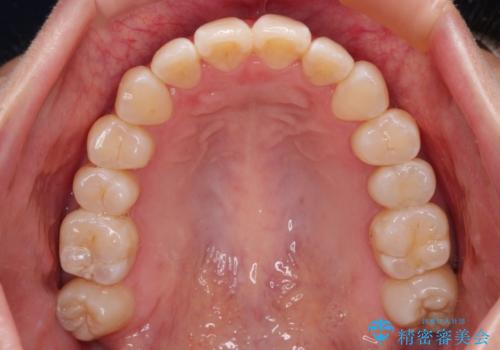

外に飛び出して磨きにくい奥歯と上下前歯の隙間 インビザラインによる矯正治療

- 上下前歯の隙間と、外側を向いていて歯磨きのしにくい奥歯を気にして来院された患者様です。

下顎前歯が1本欠損しており、上下アーチはアンバランスとなりますが、インビザラインを用いて上下の隙間を改善しながら歯列を整えることとしました。

外側を向いている奥歯は、内側にアンカースクリューを埋入して牽引の固定ゲント氏、部分的にワイヤー装置を用いることで歯列に納めることとしました。

下顎前歯の1本欠損により左右の咬合が不安定となり、治療経過で噛みにくい状態が続きましたが、最終的には違和感なく噛めるようになりました。